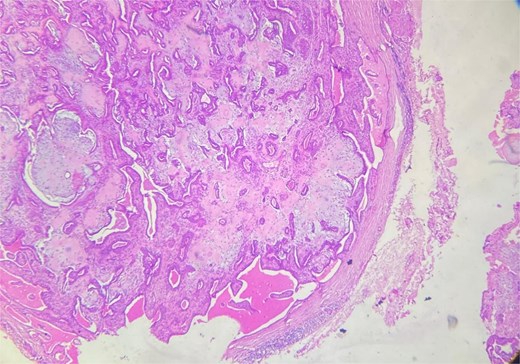

A 48-year-old Moroccan woman, with no significant medical history, presented with a nodule on the infraorbital rim evolving over 1 year without associated symptoms. Clinical examination revealed a 0.7 cm nodular swelling at the infraorbital rim below the lower eyelid. It was mobile and skin-colored, without inflammatory signs. Ophthalmologic examination was unremarkable. Lymph nodes and salivary glands were normal. An excisional biopsy of the mass was performed. Macroscopically, it was a 0.7 cm beige, firm nodule. Microscopic examination showed a well-circumscribed benign tumor proliferation (Fig. 1) composed of tubules, ducts, and cysts lined by a bilayered epithelium. The cells exhibited no nuclear atypia. The stroma was fibromyxoid with chondroid foci. There was no perineural invasion or vascular emboli, and surgical margins were clear. Given this typical microscopic appearance, no additional studies were indicated, and the final diagnosis was CS. Postoperative recovery was uneventful, and no further follow-up or additional examinations were necessary.